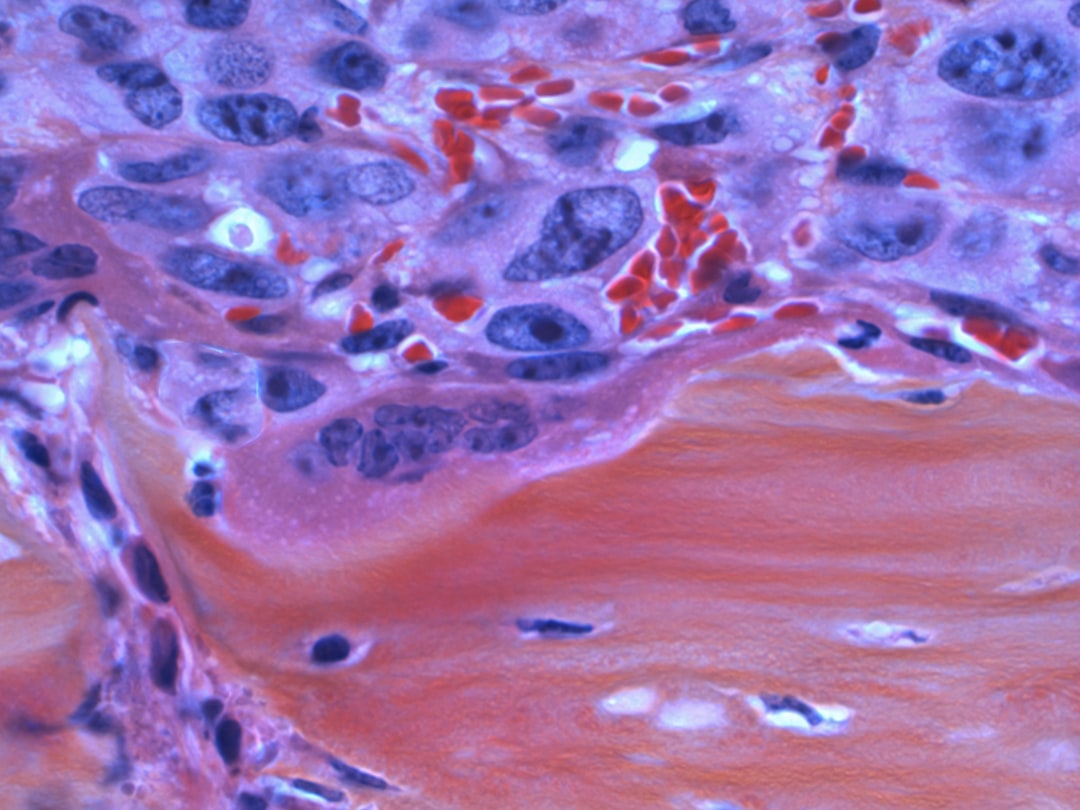

또한, 소변이나 배변 시 불편함도 일어날 수 있습니다. 이는 난소가 크기 때문에 인근 장기와 신경에 영향을 줄 수 있기 때문입니다. 난소종양이 의심되는 증상이 지속된다면, 초음파나 CT 촬영 등의 정밀 검사를 통해 상태를 확인해야 합니다. 이러한 증상들은 건강에 큰 영향을 미칠 수 있으므로 소홀히 여겨서는 안 됩니다.

난소종양의 치료 방법에는 여러 가지가 존재합니다. 우선, 난소종양 수술은 종양의 크기와 유형에 따라 다르게 진행됩니다. 보통 양성 종양이라면 수술을 통해 제거하는 것이 일반적이지만, 악성 종양일 경우에는 추가적인 치료가 필요할 수 있습니다. 이를 위해 환자의 상태를 면밀히 평가하는 것이 중요합니다.

난소종양에 대한 진단과 관련하여 알아두어야 할 사항들이 있습니다. 난소 물혹 양성종양 차이를 이해하기는 매우 중요합니다. 양성 물혹은 대개 증상이 없지만, 시간이 지나면서 크기가 커질 수 있으므로 관찰이 필요합니다. 반면에 악성 종양은 진단 후 즉각적인 대응이 필요할 수 있습니다.

특히 난소 경계성종양의 경우는 말 그대로 악성과 양성 사이의 상태로, 진료 시 각별한 주의가 필요합니다. 초기에는 일반적으로 치료가 가능하지만, 이를 간과할 경우 회복이 어려워질 수 있습니다. 따라서 정기적인 건강 검진이 중요한 이유입니다.